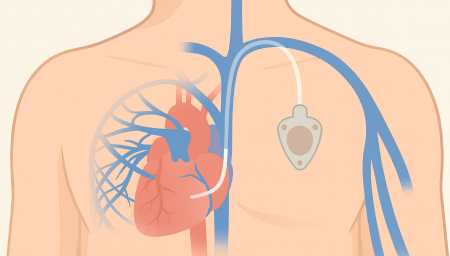

Chemoport는 항암제처럼 자극이 강한 약물을 안전하고 안정적으로 투여하기 위해

흉부 피부 아래에 이식하는 중심정맥 사용 포트입니다.

Chemoport는 항암제처럼 자극이 강한 약물을 안전하고 안정적으로 투여하기 위해 흉부 피부 아래에 이식하는 중심정맥 사용 포트입니다. 팔 혈관이 약하거나 반복 주사로 인한 통증이 걱정되는 환자에게 도움을 줄 수 있으며, 장기간 치료가 필요한 경우 편안하게 항암 치료를 지속할 수 있도록 설계되어 있습니다.

항암관(Chemoport)삽입 과정

국소마취 후 작은 절개를 시행 (보통 쇄골 아래 약 2~3cm 정도 절개)

정맥에 카테터 삽입 후 포트와 연결

방사선으로 카테터 위치 확인

피부 봉합 후 소독 드레싱